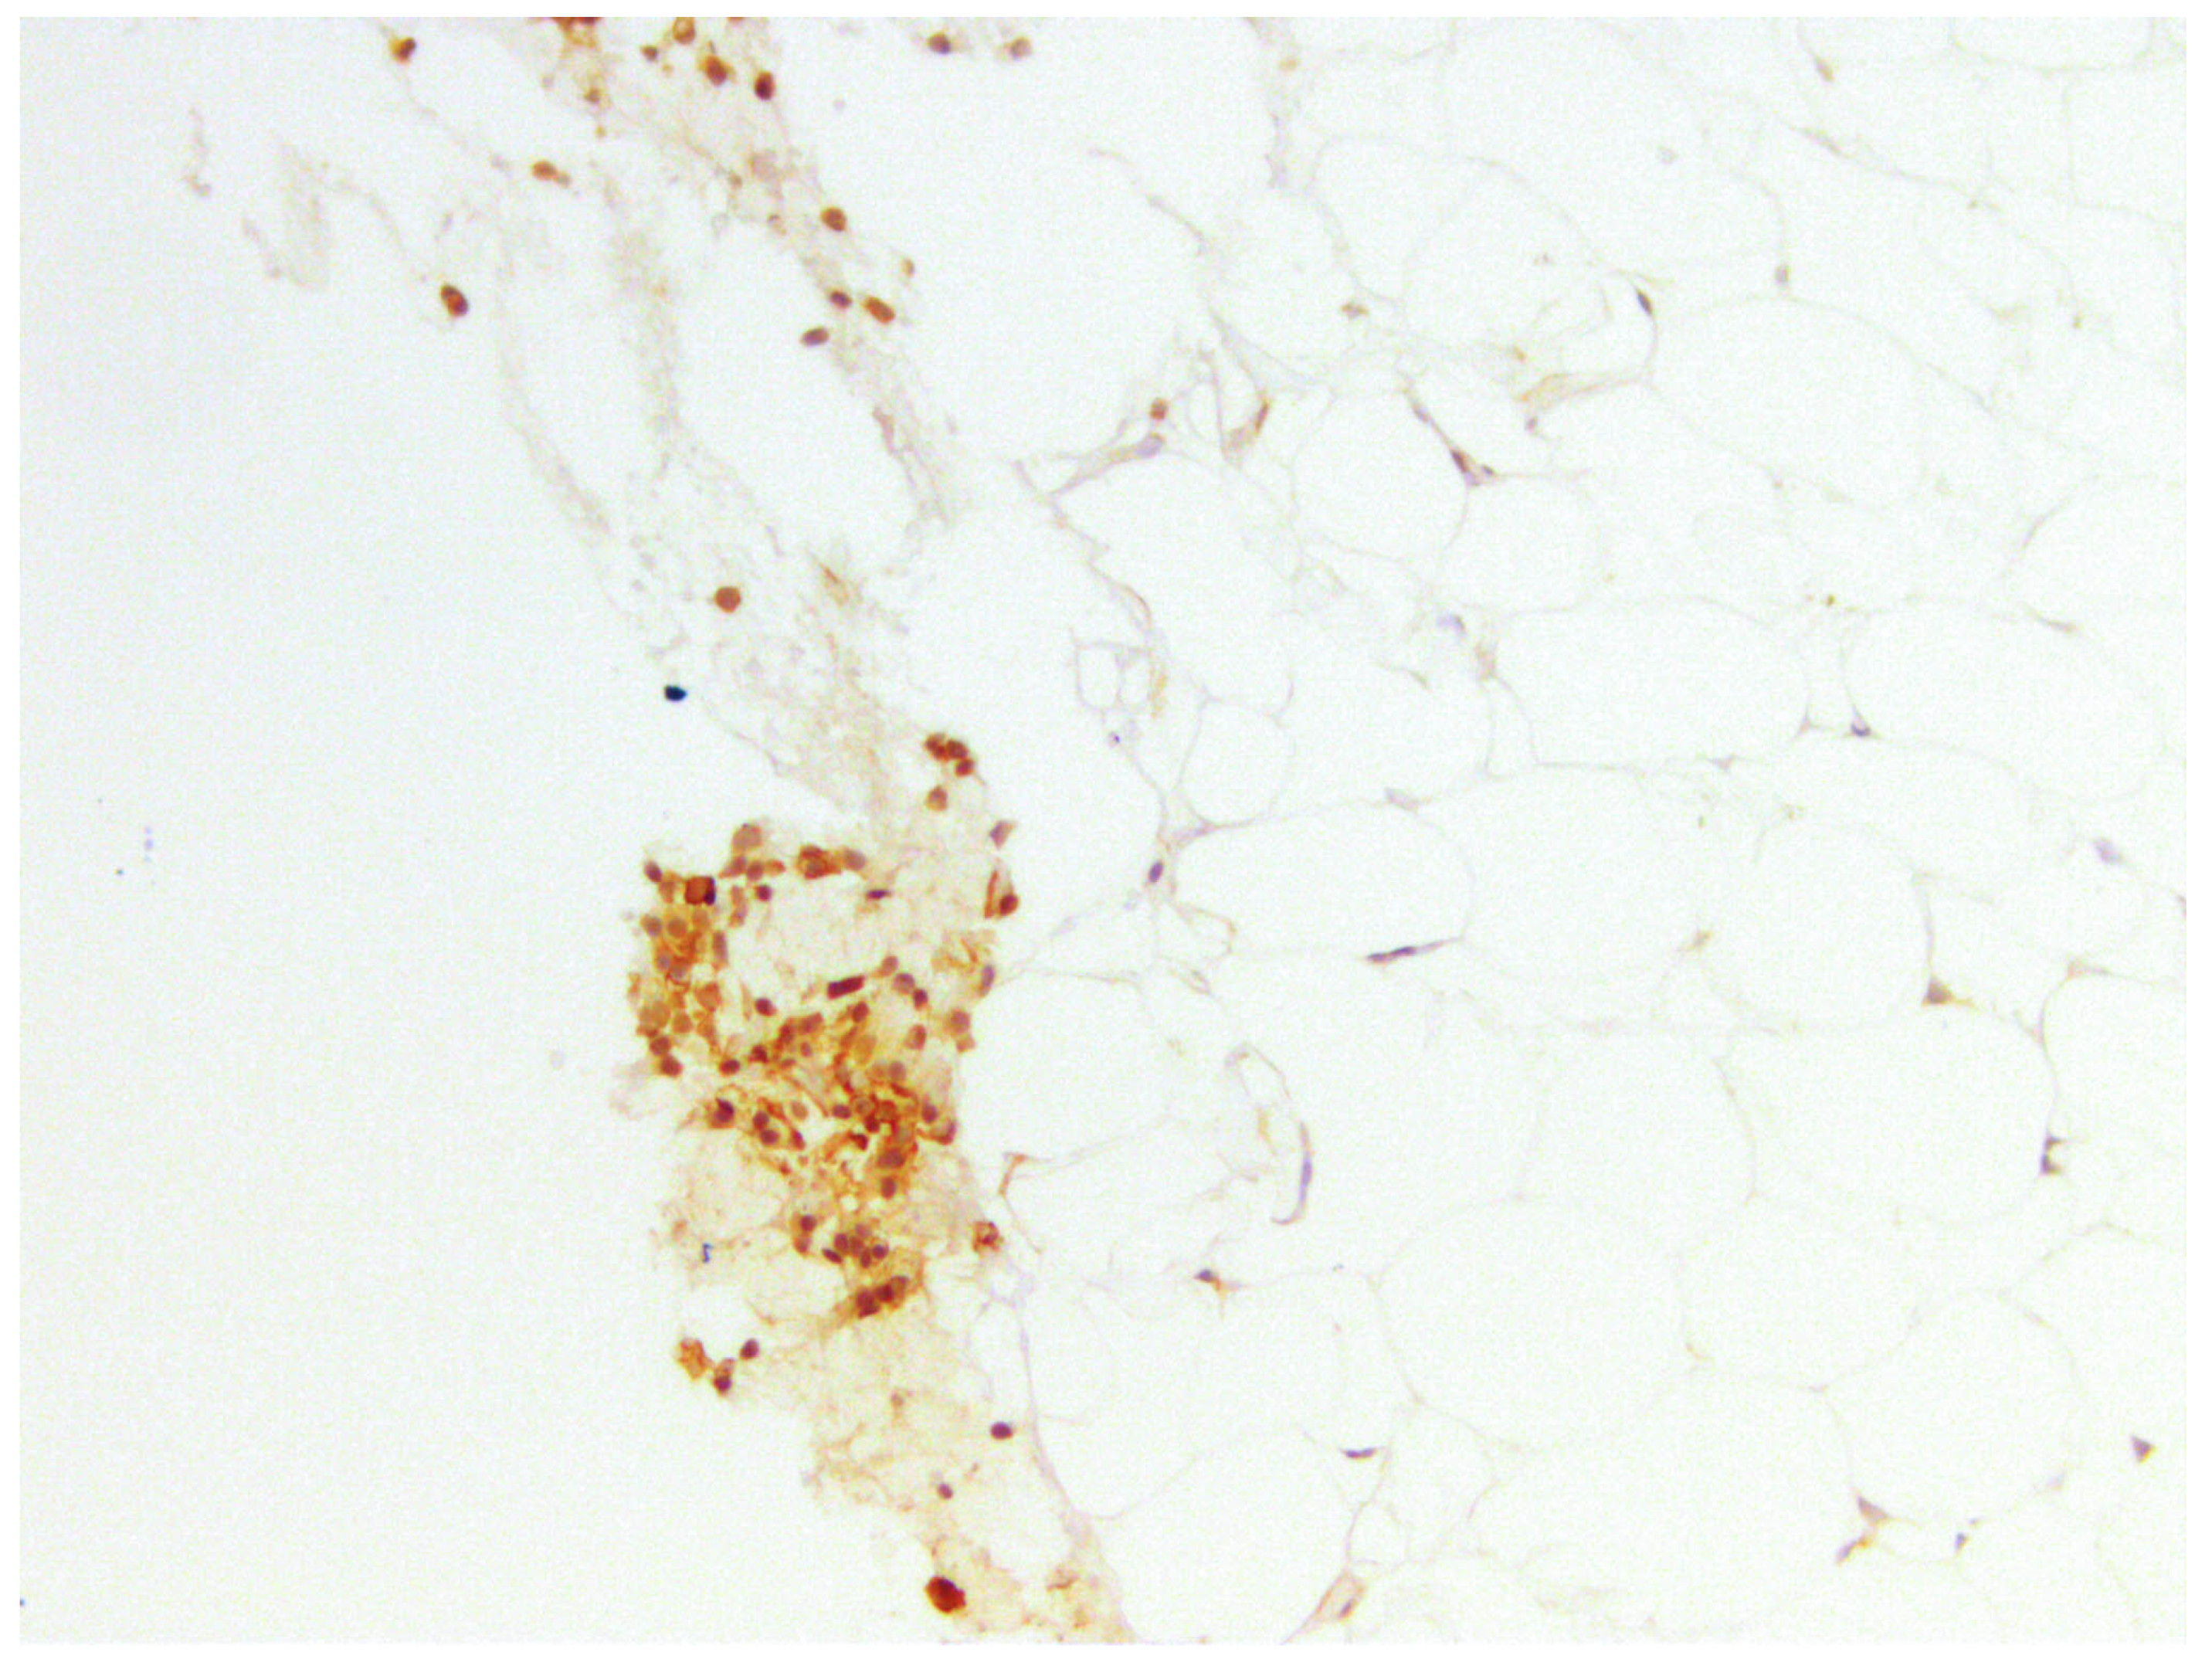

3.3.1. CD44

3.3.2. CD133

3.3.3. CD10